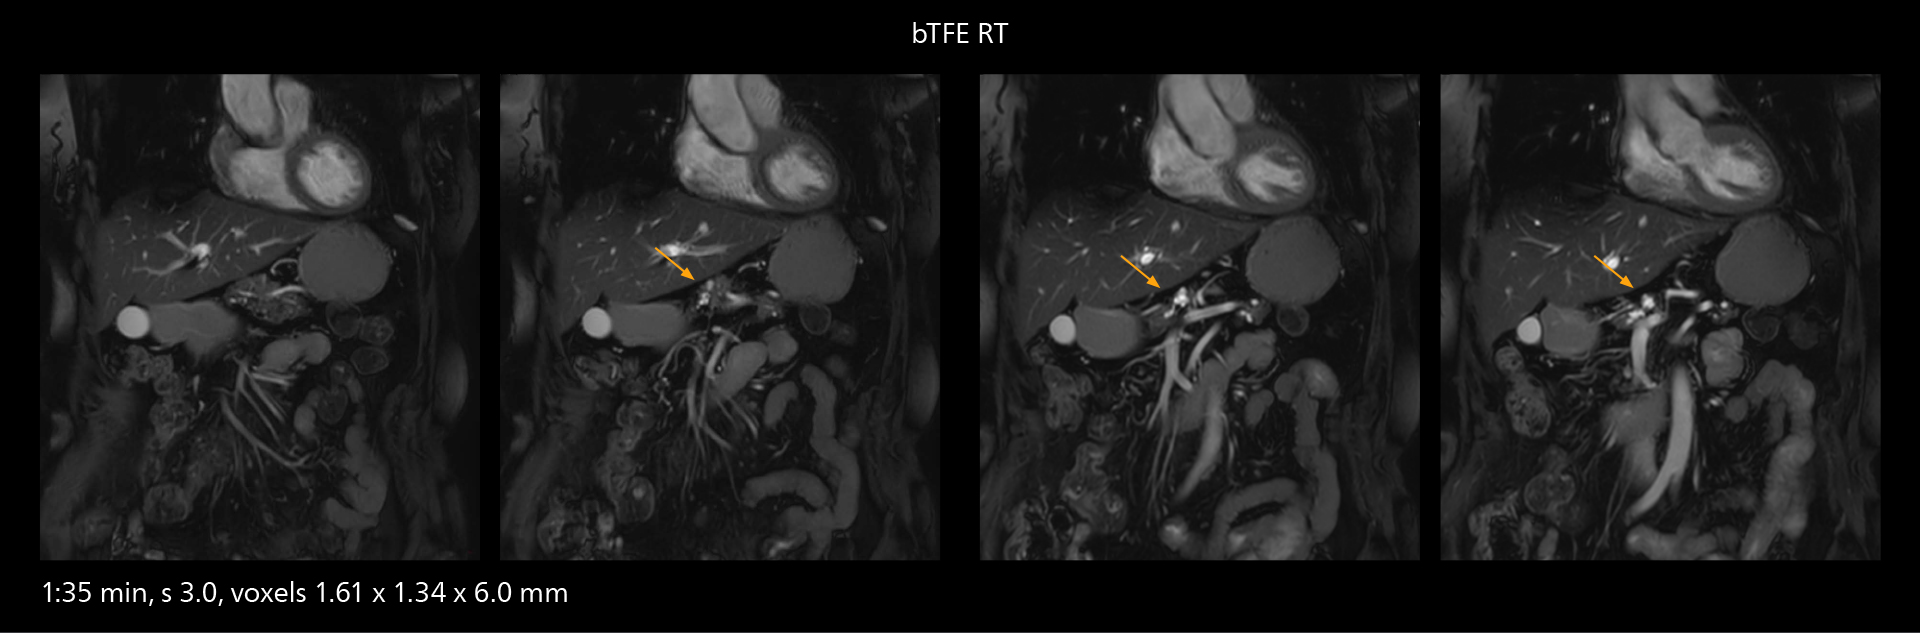

“The implementation of VitalEye respiratory synchronization has had a significant impact,” says MR technologist Yoshihiro Otsu, Chief of the Radiological Department. “It not only improves workflow, but it also has increased the quality of examinations. Particularly for the large number of MRCP examinations performed in this hospital, VitalEye has increased the possibility to obtain sharp images with less blurring. Clinicians here really appreciate this improvement in MRCP image quality.”

MRCP

With SmartPath to Elition X, the MRCP examinations at Sannodai Hospital benefit from VitalEye: respiratory synchronization is possible without respiratory belt positioning and image quality is excellent.

The value of the Elition X gradients is also evident in DWIBS studies. “The fact that we can consistently obtain distortion‐free DWIBS while reducing imaging time at three coronal stations is excellent,” Dr. Makuuchi says. “In these patients, it’s also important that the application of Compressed SENSE to T2‐weighted, STIR and mDIXON sequences has no impact on the examination time of whole‐body imaging. As a result of the increased speed and higher image quality we realize, DWIBS studies have now become routine examinations.”